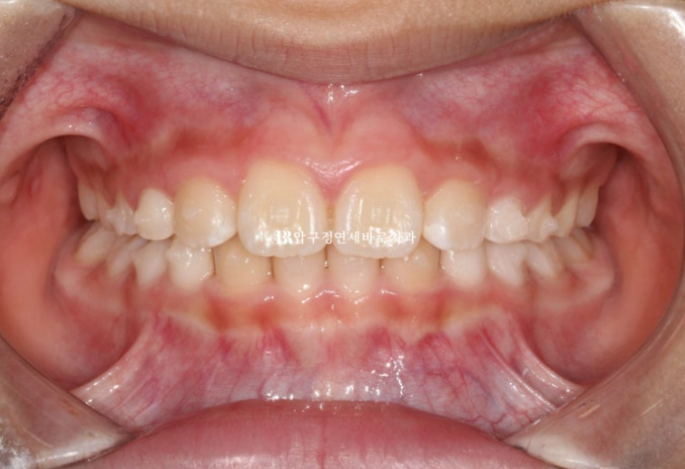

6개월의 교정 9개월의 MA 총 15개월간 57개 장치를 다 낀 후 모습입니다.

24.06

53단계부터 57단계까지 마지막 5개 장치를 어금니쪽 장치를 잘라 끼면서 교합 안정화를 도모했고 지난 2월 사진과 다르게 이제 어금니가 잘 닿습니다.

뿐만 아니라 윙을 잘라내어 한달 이상 꼈는데도 아래턱이 다시 뒤로 밀려서 물리거나 하지 않고 아래턱의 위치가 아주 안정적임을 확인했습니다.

이제 치료 전 후 비교 보겠습니다.

총 치료 기간은 22개월 입니다.

23.04~25.01

가지런해진 앞니와 영구치를 위한 충분한 공간

윗니 돌출이 많이 개선이 되었습니다.

튀어나온 윗니가 뒤로 들어갔나? 싶겠지만 사실은 위니가 뒤로 들어간 것이 아니라

아랫니를 품은 아래턱뼈가 성장하여 앞으로 나온 것 입니다.

안모의 개선

치료 전 골격성 무턱을 나타내는 ANB 라는 수치는 6.1이었으나 3.9로 정상범위가 되었고 위턱과 아래턱의 성장이 바람직하게 일어났습니다.